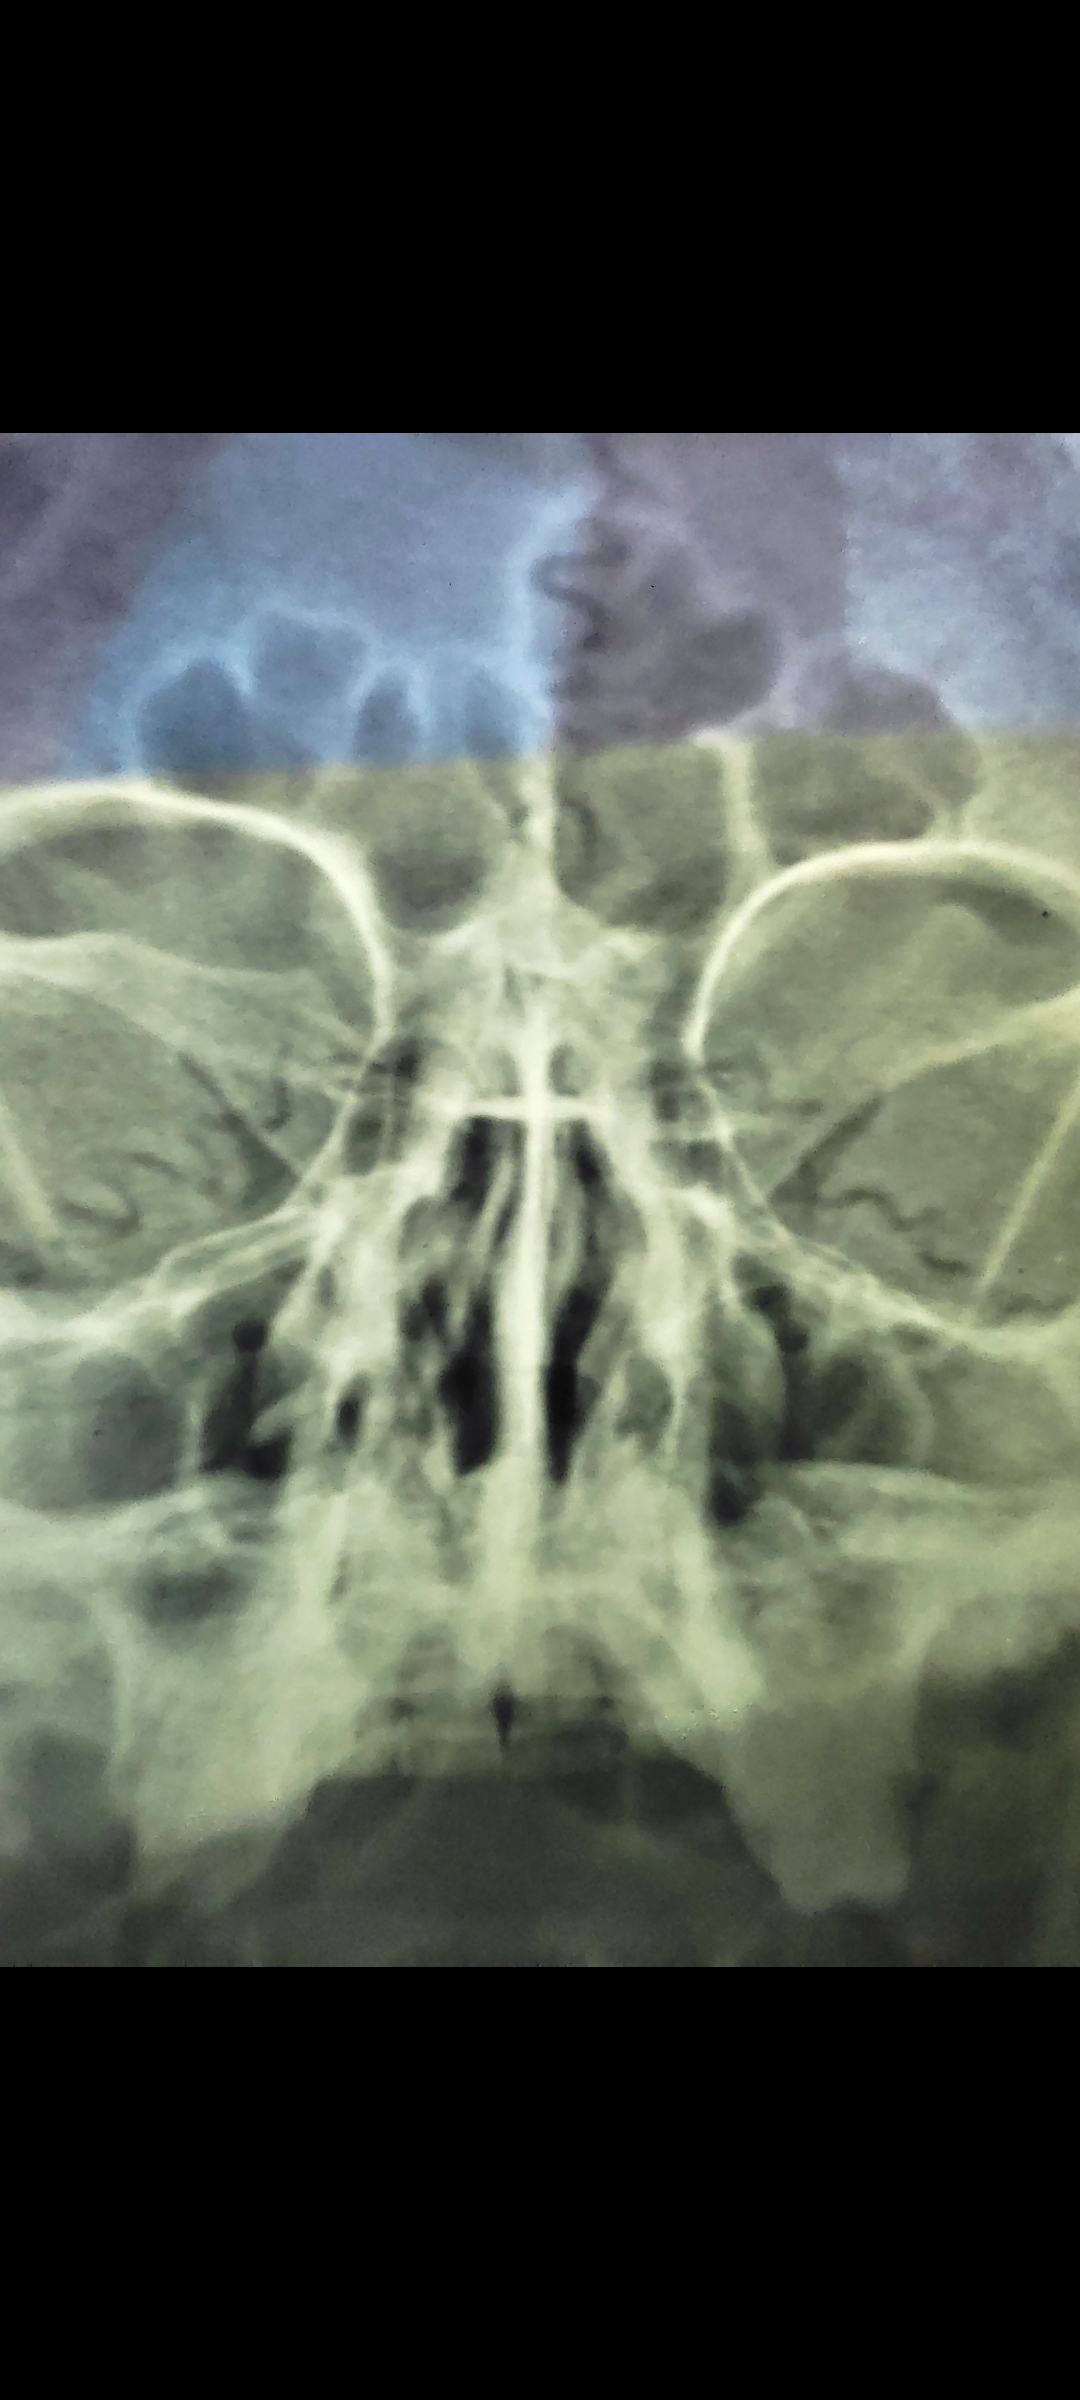

Salam everyone Doctor told me that I am suffering from sinusitis infection that has created problem with your nose bone which is diagnose in an x-ray scan. I have problem with breathing, severe headache and fatigue. Please suggest suitable treatment and give your finding on x-ray. Regards Tayyab

Attach Photo here: